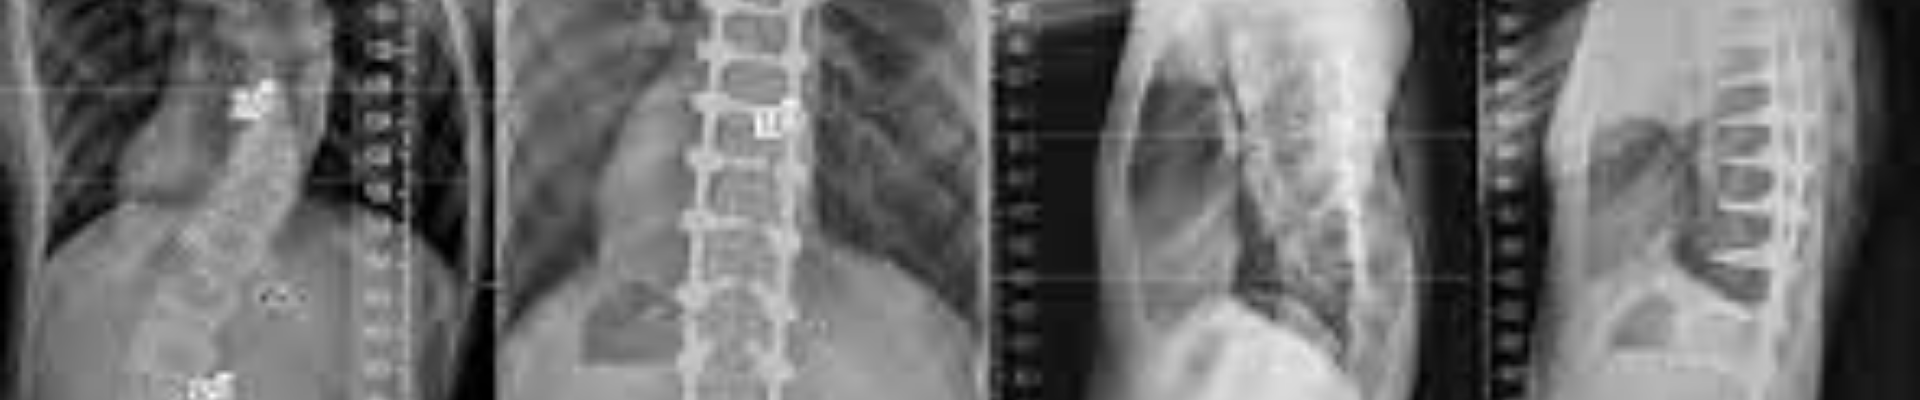

العمود الفقري الطبيعي يكون مستقيمًا من الخلف ويكون مائلًا قليلًا إذا نظرت له من الجنب، وفي بعض الحالات يتعرض الشخص لخلل أو اضطراب يسبب اعوجاج في العمود الفقري، ويوجد ثلاثة أنواع منه:

الحداب

- يصاب الشخص بالحداب عند التقدم في العمر، ويمكن أن تظهر بعض الخضوع إلى عملية جراحية.

- الحداب عبارة عن اعوجاج في المنطقة أعلى الظهر، وهذا يؤدي إلى الشعور بصعوبة في الوقوف بشكل مستقيم.

- في الحداب تصل درجة الاعوجاج 50 درجة.

اعوجاج العمود الفقري جانبيًا

- يتعرض الشخص لاعوجاج العمود الفقري جانبيًا عندما تبدأ المفاصل الخاصة بدعم ومساندة الفقرات في الميل قليلًا وهنا يحدث انحراف مسار الفقرات وفي النهاية يصاب الشخص باعوجاج في العمود الفقري جانبيًا.

اعوجاج العمود الفقري للداخل

- اعوجاج العمود الفقري للداخل يتمثل في انحنائه واعوجاجه في المنطقة أسفل الظهر ولكن للداخل.